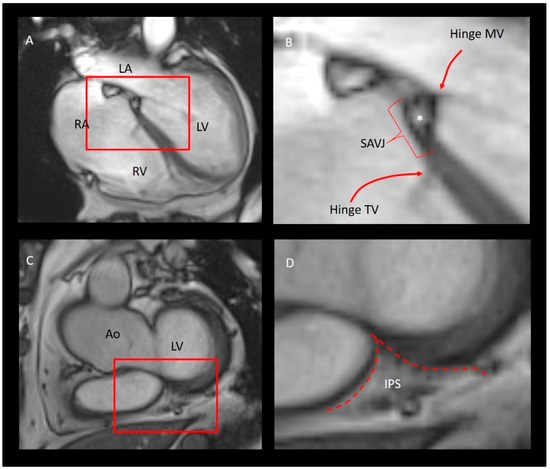

3. Does the Tricuspid Annulus Exist?

The “Mural” Annulus

4. The “Septal” Annulus

7. What Are the Similarities and Differences between the Tricuspid and Mitral Valve